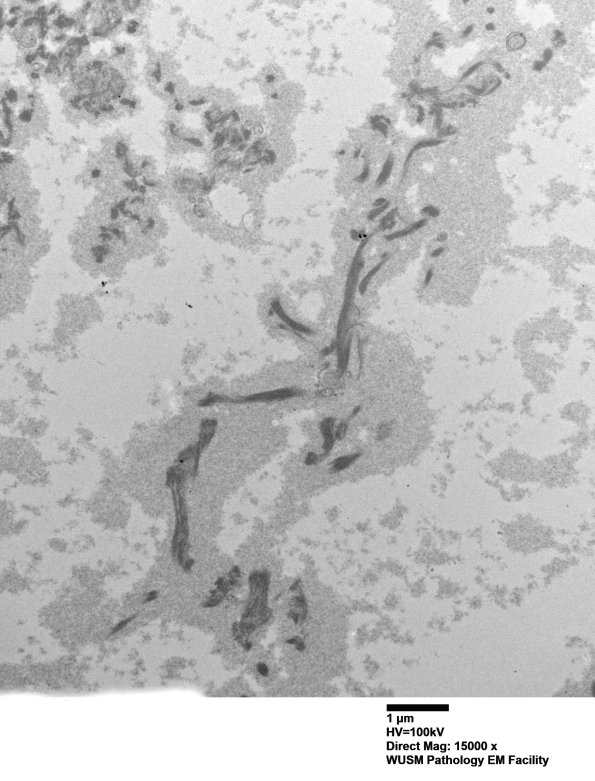

6B1-3 Various magnifications of the subperineurium in this case shows granular pale oxytalan and elastin aggregates. (electron micrographs)